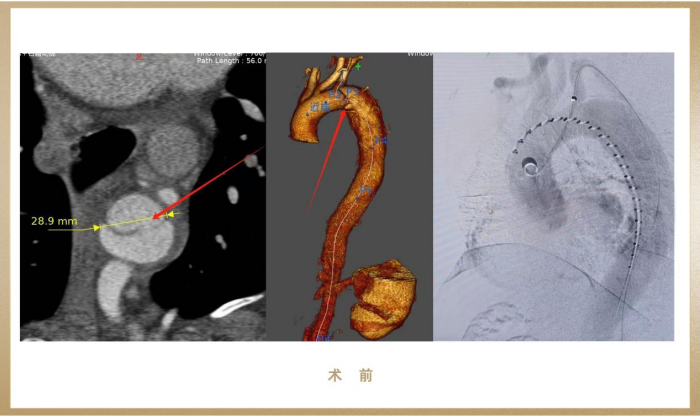

患者为一名37岁藏族男性,因剧烈胸痛垂危入院,术前CTA提醒Stanford B型自动脉夹层,破口近左锁骨下动脉,夹层动脉瘤最大径达38mm,一旦分裂会在短功夫内引发大出血、休克甚至殒命,情况极度危机!

(图:术前影像)